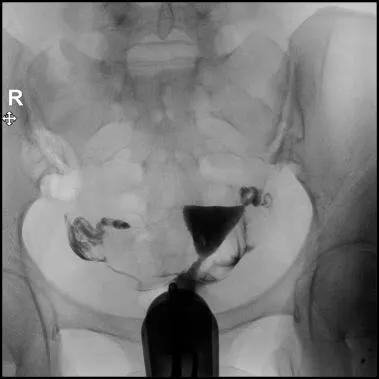

8.透视下注对比剂,动态观察造影剂逐渐膨胀宫腔,流入输卵管,经过伞端流入盆腔的全过程,同时拍摄X光片;

定位片

充盈片